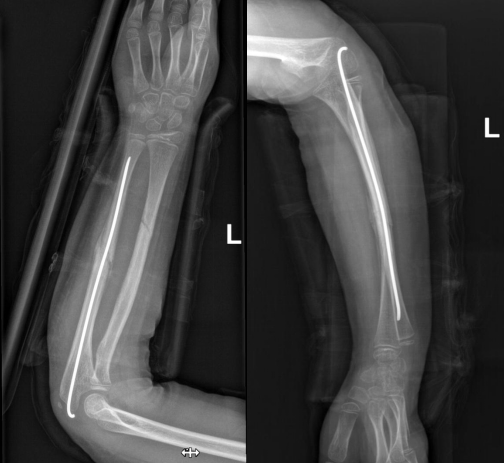

经手法复位治疗无效,几经辗转多家医院都表示需要切开手术治疗。龙泉驿区中医医院骨伤一科许锦涛主任带领团队详细研究病情,聚焦患者核心问题,决定为其实施微创手术——弹性髓内钉(ESIN)内固定术。

弹性髓内针技术具有创伤小、固定简便可靠、愈合快、住院时间短等特点,既固定了骨折

又不影响肢体美观,可谓一举两得。黎同学的手术过程十分顺利,骨折端对位对线良好,术后伤口仅1厘米,患者在平稳康复中。

术后骨折断端移位好转,力线纠正